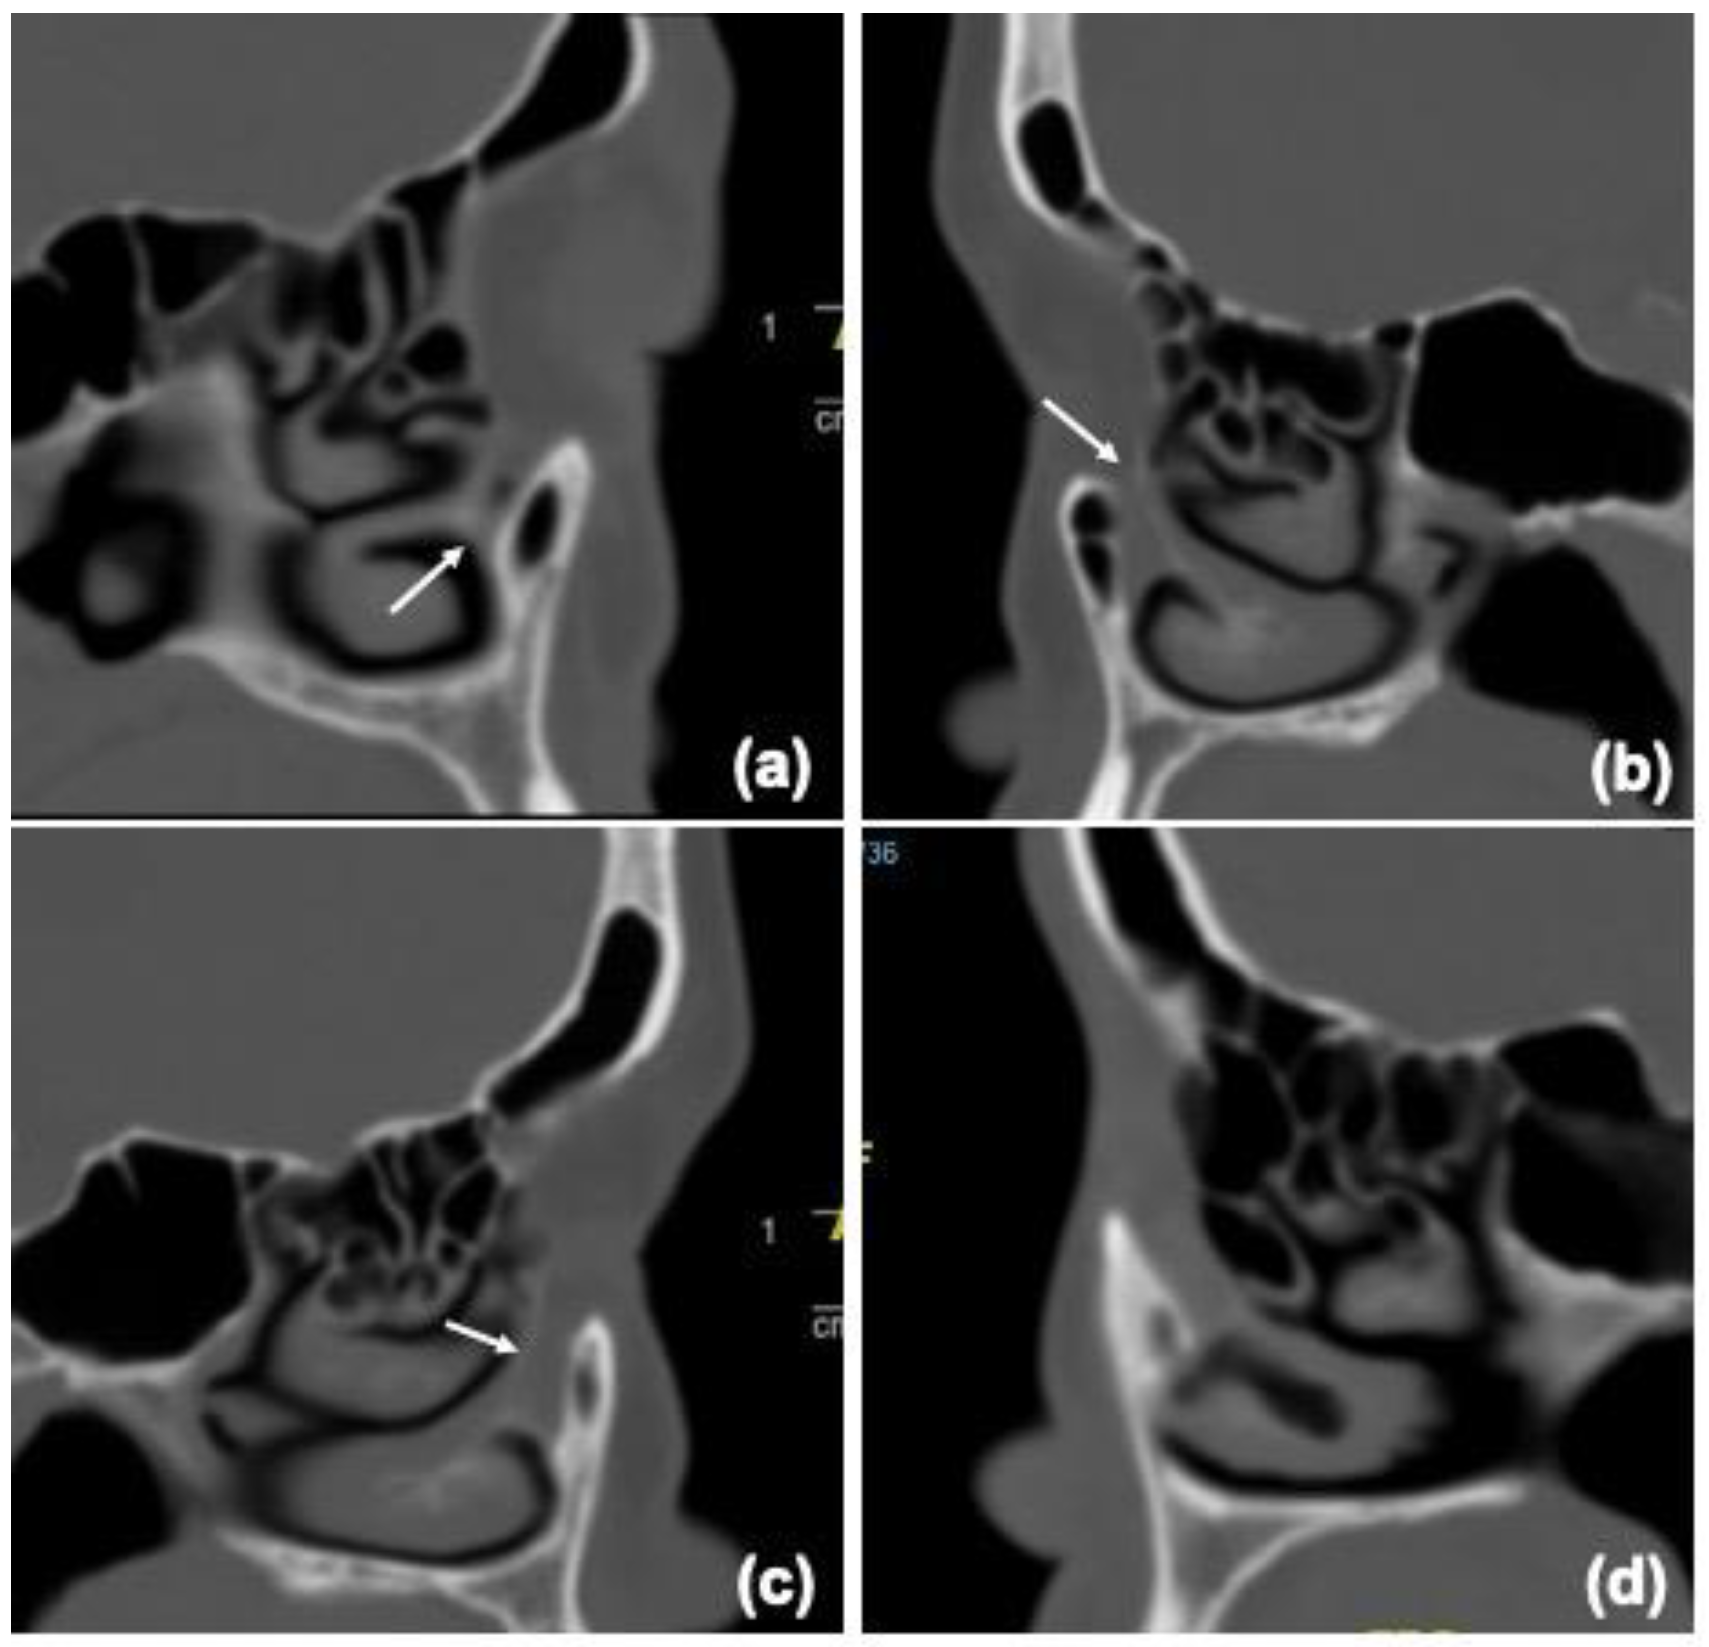

| Columnar | 24 | 48 | 33 | 66 |

| Flare | 17 | 34 | 11 | 22 |

| Funnel | 4 | 8 | 2 | 4 |

| Hourglass | 5 | 10 | 4 | 8 |